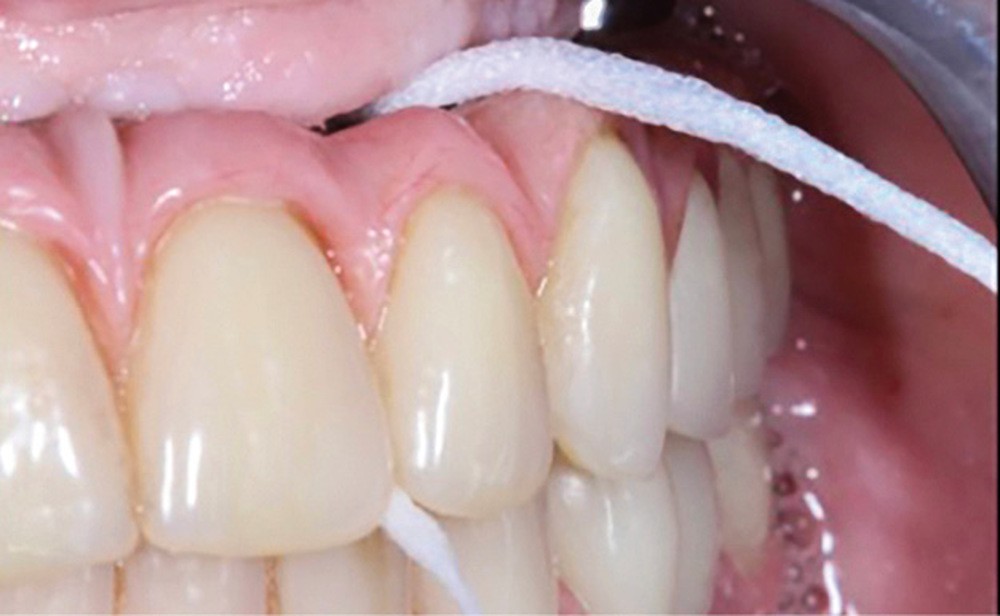

Le projet prothétique pré-implantaire [11] est également l’une des clés du succès ; il doit permettre un positionnement tridimensionnel optimal de l’implant, notamment avec un environnement tissulaire adéquat ; selon la littérature, 2 mm de tissu kératinisé sont nécessaires autour des implants pour fonctionner comme un bouclier autour de lui [12] (fig. 3).